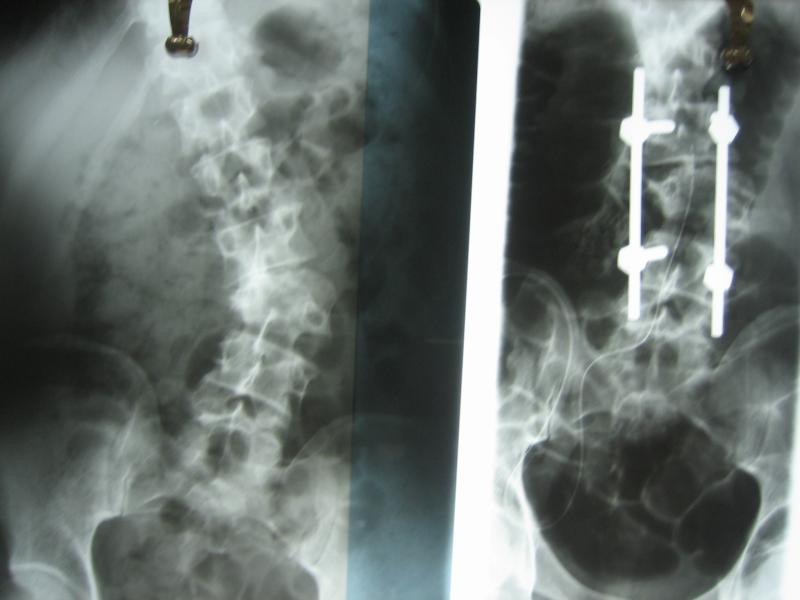

the decompressed spinal cord.

post op deformity correction

posterior fusion mass